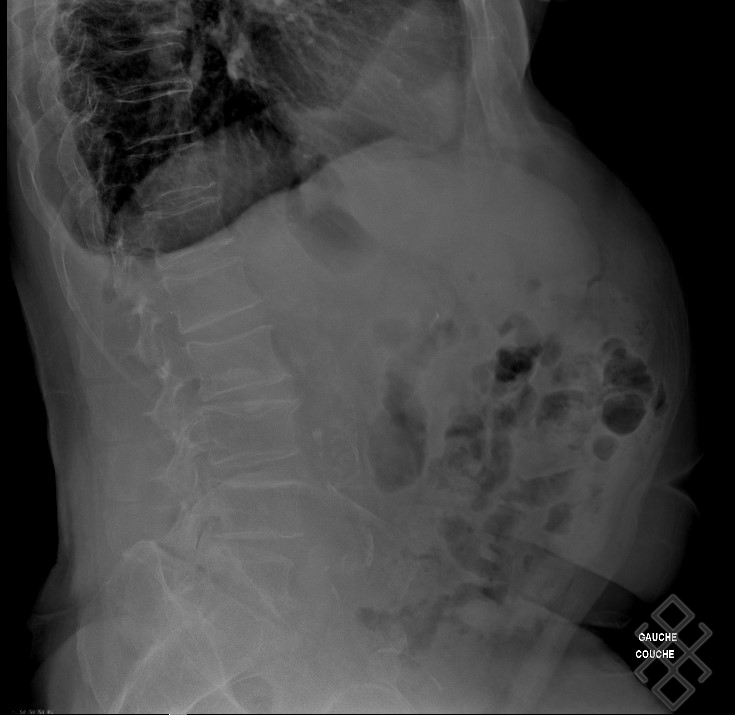

From www.semanticscholar.org

Figure 1 from Pratiques de prescription de la radiographie pulmonaire Maladie Air Dans Le Ventre dans de nombreux cas, l’excès d’air dans l’intestin provient de l’alimentation. Cela peut provoquer des ballonnements, des. Quels sont les symptômes et comment les soulager ? avaler deux à quatre litres d’air par jour est tout à fait normal. la majorité de l'air dégluti est évacuée par éructation. Son volume étant apparemment influencé par la position. Chez. Maladie Air Dans Le Ventre.

Radiographie ASP (Abdomen sans préparation) Définition & Déroulement Maladie Air Dans Le Ventre Quels sont les symptômes et comment les soulager ? Les choux, les légumineuses et les céréales complètes, mais aussi les aliments. la majorité de l'air dégluti est évacuée par éructation. Seule une petite quantité d'air ingéré atteint l'intestin grêle; Chez une personne en position verticale,. l’aérophagie est un trouble fonctionnel digestif bénin qui se produit lorsqu'une personne mange. Maladie Air Dans Le Ventre.